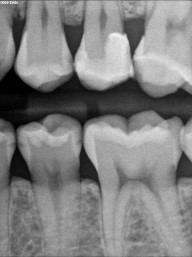

Patient 4: Teeth #12 and #13

On the black-and-white image, the patient has caries on #12, #13, #18, #19 and #20. We will focus on #12 and #13, especially the mesial of #13. The black-and-white image is less suggestive there than on #12. The photo tells a very different story. #13 is more advanced.